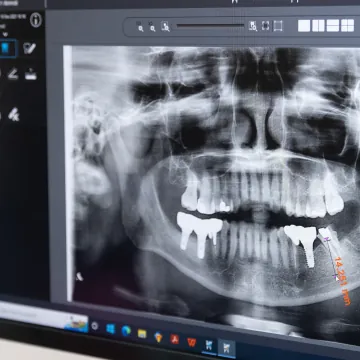

Advanced Technology

We always make sure that our equipment, technology and knowledge are always up to date. Whether an equipment to identify abnormal chewing pattern to get to the root cause of your problem, a 3D X-ray to help plan the treatment or a laser to help your bone heal faster, all of these are there to make sure you get the best treatment from us. With an expert fully equipped with latest equipment, you can rest assure that you are in good hands.

We begin your journey with an oral health assessment to understand your dental concerns and medical history. An impression and X-ray will be taken during the assessment process. Based on your dental health and symptoms, we will then recommend you the best treatment plan.